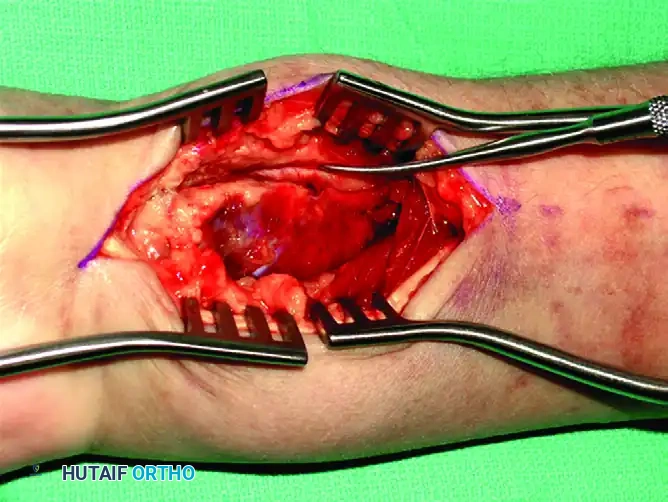

Pronator Quadratus Elevation: Using a Freer elevator or electrocautery, the pronator quadratus is elevated from its radial insertion in an L-shaped fashion, reflecting it ulnarly.

Fracture Exposure and Reduction: The fracture line is now fully exposed. Hematoma is evacuated, and the fracture is reduced under direct vision and fluoroscopic guidance.

Plate Application: A pre-contoured volar locking plate is positioned proximal to the watershed line to prevent flexor tendon irritation. The first screw is inserted into the elongated gliding hole in the radial shaft to allow for proximal-distal adjustments.